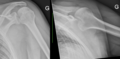

- Différentes lésion labrales post.jpg Alexandre.laedermann

19:53, 26 January 2020

1,918 × 454; 739 KB